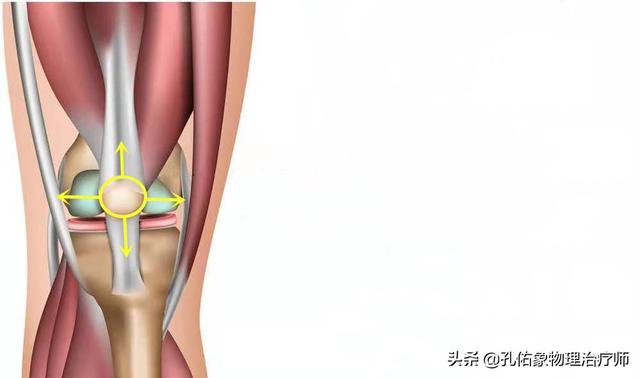

Wenn wir das Knie strecken, werden wir feststellen, dass sich die Kniescheibe mit der Beugung und Streckung unseres Kniegelenks bewegt, und das Geräusch, das entsteht, wenn das Gelenk gebeugt und gestreckt wird, hängt tatsächlich mit der Bewegung der Kniescheibe zusammen. Unterhalb der Kniescheibe befindet sich ein so genannter infrapatellarer Fettkörper, der ein wichtiger Teil der Struktur der Kniegelenksstreckung ist. Der infrapatellare Fettkörper hat eine dämpfende Wirkung bei der Bewegung und sorgt dafür, dass die Kniegelenksstreckungsbewegung reibungslos verläuft.

Im Allgemeinen kann diese Art von Struktur bei wiederholtem Gebrauch des Kniegelenks zu einer gewissen Abnutzung führen, die sich auf die Bewegung auswirkt, was sich unter anderem in einem klappernden Geräusch äußern kann.

Das Kniegelenk ist in seiner Art, Gewicht zu tragen, einzigartig, und seine Belastung nimmt bei sozialen Aktivitäten und Sport erheblich zu. Damit das Kniegelenk sowohl flexibel als auch belastbar ist, ist die komplexe Struktur der umgebenden Muskeln entscheidend. Kalte und schmerzende Knie sowie Knackgeräusche lassen sich gut durch die Struktur des Kniegelenks erklären.

Wir sind auf unsere beiden Beine angewiesen, um gehen zu können, also müssen wir unsere Kniegelenke strecken, um unseren Schwerpunkt zu verlagern. Das Knie kann zwar nach hinten gebeugt werden, aber nach vorne und zu den Seiten hin gibt es im Prinzip keine Beweglichkeit, um die Stabilität unserer Kniegelenke zu erhalten. Die Grundlage für die Aufrechterhaltung dieser Stabilität liegt in den vier unverzichtbaren Elementen des Kniegelenks:

(i) der Quadrizeps-Muskel als Kraftquelle; (ii) die Kniescheibe; (iii) die Patellasehne; und (iv) der Angriffspunkt des Schienbeinhöckers.